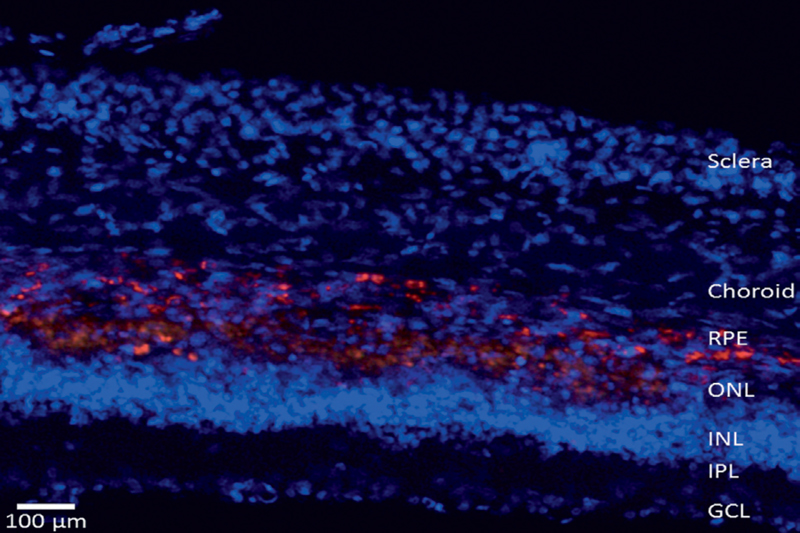

We also have preliminary clues on the role of photogenerated charges in the photo-transduction process and in the resulting neuronal activation. In view of therapeutic applications to human diseases, nanoLight PNTs will target photoreceptor degeneration in Retinitis Pigmentosa (RP) and age-related macular degeneration (AMD).